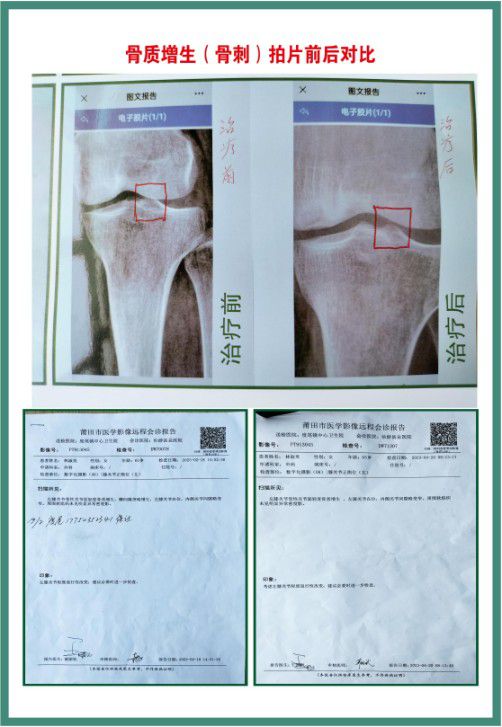

09年国务院22号文件和(52号)令,响应发扬传统中医中药精神,促进中医药事业发展。2010年进入北京翰林职业研修学院中国首届中医中药传承学习,颁发:“特效医术专业人才”,14年参加中国中医第二届养生论坛。同年特邀第五届全国名老中医临床特效技术论坛。授予:名老中医牌匾。15年申请专利5项,①灭癌精口服液(防癌,抗癌,灭癌,药食同源)②骨质增生,(骨刺)③鼻炎液④骨头疼痛液⑤颈腰椎间盘突出等病症,简单易用,方便受到人民的喜爱,不动手术,不吃药,不打针,排除动手术的风险,减轻费用。不拿国家发明专利奖金,和国家立项补贴,为国贡献。研发药食同源(心脑血管)等疾病。